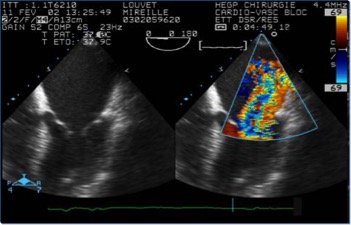

L’area del jet di rigurgito, esaminata al color-doppler , è uno dei parametri più usati, soprattutto quando espressa in rapporto all’area dell’atrio sinistro.

Il diagramma mostra la valutazione della severità dell’insufficienza mitralica usando l’approccio transesofageo con vista asse-lungo. La gravità dell’insufficienza mitralica (1-4+) viene stabilita in base alla lunghezza e alla larghezza del flusso di jet nell’atrio sinistro. LA, atrio sinistro.; RV, ventricolo destro; LV, ventricolo sinistro.